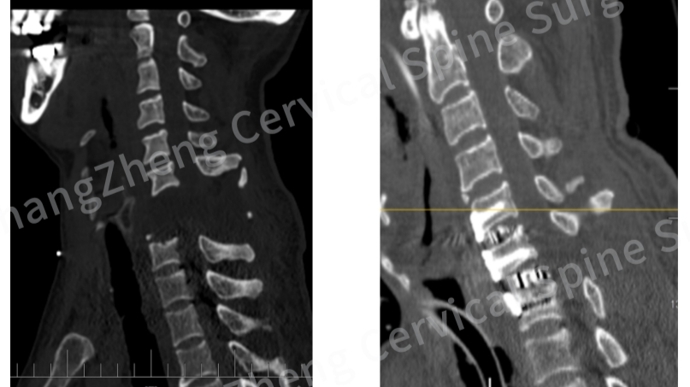

影像学检查的结果令人窒息:颈椎发生了极其罕见的大跨度脱位,严重程度犹如“身首离断”,脊髓严重挫伤,关键神经血管结构撕裂。雪上加霜的是,骨折脱位区域形成的巨大血肿,以及双侧椎动脉因损伤而闭塞,让患者的血压如同失控的过山车,频繁骤降至约50mmHg的危险值,全靠大剂量升压药物在生死边缘勉强维系循环。

无影灯下,医生们踏上的是一条充满未知与凶险的征途。首要威胁悬在头顶:椎动脉大出血。CT造影显示,患者右侧椎动脉断裂,幸被骨折组织和血凝块暂时封堵;左侧椎动脉则被牵拉得“像一根被拉长的细管”,仅存一丝脆弱血流。“椎动脉压力很高,术中一旦血凝块松动,几秒内失血可达1000至2000mL,人可能瞬间就没了。”陈华江深知其险。更令人揪心的是,患者伤情过重,连完善检查都成奢望,“稍一挪动,血压就掉到50mmHg以下”。这意味着手术团队将在未知中“走一步、看一步”。

复位与重建的难题同样棘手。患者颈椎前后连接尽断,常规方案需前后路联合,但其颈后皮肤大面积破损,后路手术极易引发致命颅内感染。加之血压如风中残烛,俯卧位呼吸挑战巨大。反复权衡后,团队毅然拍板:挑战一期高难度前路手术。

历经约3小时惊险鏖战,关键突破降临!团队不仅精准复位了完全离断错位的颈椎,更创新性地应用了“卫星钢板”技术。在仅有24至26mm宽的椎体上,他们成功植入双钢板加双融合器,巧妙增加辅助钢板,实现了前路一期的超强稳定。它如同定海神针,为濒临崩溃的颈椎提供了关键的即刻稳定,避免了二次手术的巨大风险。“这一技术应用在此类极端病例中尚属首创。”陈华江介绍。